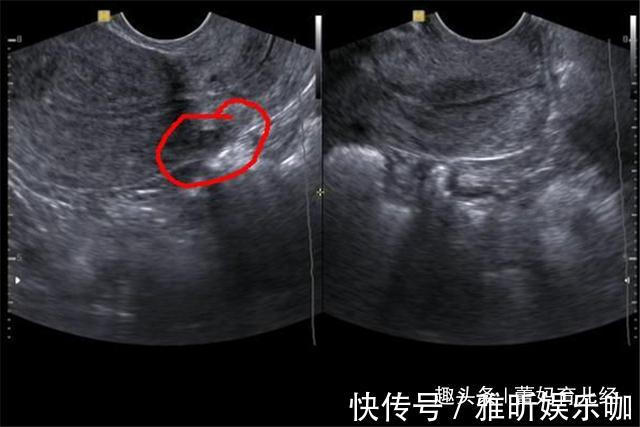

文|蕾妈育儿经(专注优质原创文章,拥有本文章版权,欢迎转发分享)养一个孩子不容易,从怀孕那一刻母亲就要注意很多细节,吃喝玩乐不能再像以前一样,稍有不慎就会导致胎儿死亡。我们都知道怀孕最关键的时期是前期,前3个月要是稳定了,胎儿流产的几率就会降低,但这不是说胎儿越往后就会越安全,母亲的行为直接影响着孩子能否安全降生。小玲平时就非常嘴馋,但怀宝宝的时候家里人管的很严,所以说馋了很久。怀孕7个月的时候,正巧遇到了同事聚会,小玲就借此机会大吃一顿,瞒着丈夫烤肉和海鲜吃了很多,但也正是因为这一顿聚餐,小玲被弓形虫感染,导致宝宝停止了胎动,最后被迫去医院做了引产,因为过于悲愤,小玲得了抑郁症。

3、饮食与精神问题孕妇怀孕期间免疫力低,如果经常吃烤肉和海鲜就容易被弓形虫感染,就算没有感染,一旦腹泻也容易流产,虽说这是偶然性的,但各位宝妈不要像小玲那样有侥幸心理。此外像焦虑和睡眠不好等精神问题会导致免疫功能紊乱,胎儿缺氧就会出现胎心停止等问题。